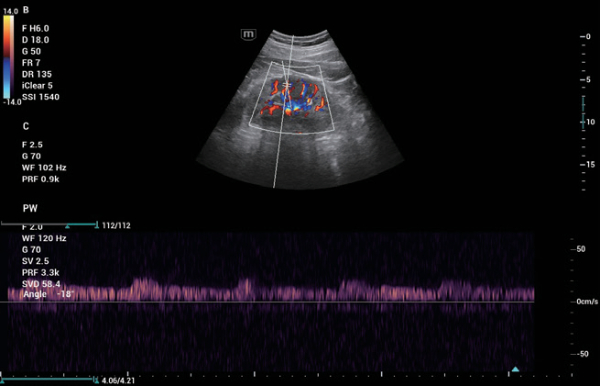

A linha Consona apresenta solu??es inovadoras e eficientes que o ajudam a realizar diagnÃģsticos em diversos tipos de pacientes.

N?o importa se sua rotina ÃĐ em hospitais, clÃnicas ou se vocÊ estÃĄ aprimorando habilidades em Imagem Geral, SaÚde da Mulher ou na ÃĄrea Cardiovascular; vocÊ encontrarÃĄ ferramentas altamente poderosas disponÃveis para manter-se na vanguarda.

Solu??es abrangentes de imagens com tecnologia ZST+

A plataforma ZST+ ÃĐ uma inova??o extraordinÃĄria, representando a evolu??o do ultrassom. Transformando as mÃĐtricas de ultrassom: da forma??o convencional do feixe ao processamento baseado em dados de canais. Supera a limita??o de compensa??o tradicional entre resolu??o espacial, resolu??o temporal e uniformidade de tecido, oferecendo qualidade de imagem excepcional para solu??es de imagem infinitas com melhorias inigualÃĄveis.